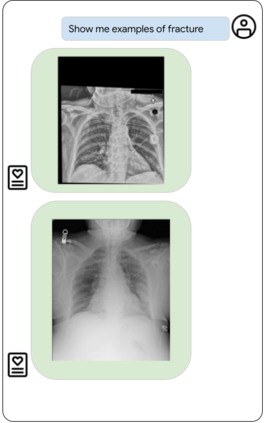

Our approach, which we call Embeddings for Language/Image-aligned X-Rays, or ELIXR, leverages a language-aligned image encoder combined or grafted onto a fixed LLM, PaLM 2, to perform a broad range of tasks. We train this lightweight adapter architecture using images paired with corresponding free-text radiology reports from the MIMIC-CXR dataset. ELIXR achieved state-of-the-art performance on zero-shot chest X-ray (CXR) classification (mean AUC of 0.850 across 13 findings), data-efficient CXR classification (mean AUCs of 0.893 and 0.898 across five findings (atelectasis, cardiomegaly, consolidation, pleural effusion, and pulmonary edema) for 1% (~2,200 images) and 10% (~22,000 images) training data), and semantic search (0.76 normalized discounted cumulative gain (NDCG) across nineteen queries, including perfect retrieval on twelve of them). Compared to existing data-efficient methods including supervised contrastive learning (SupCon), ELIXR required two orders of magnitude less data to reach similar performance. ELIXR also showed promise on CXR vision-language tasks, demonstrating overall accuracies of 58.7% and 62.5% on visual question answering and report quality assurance tasks, respectively. These results suggest that ELIXR is a robust and versatile approach to CXR AI.